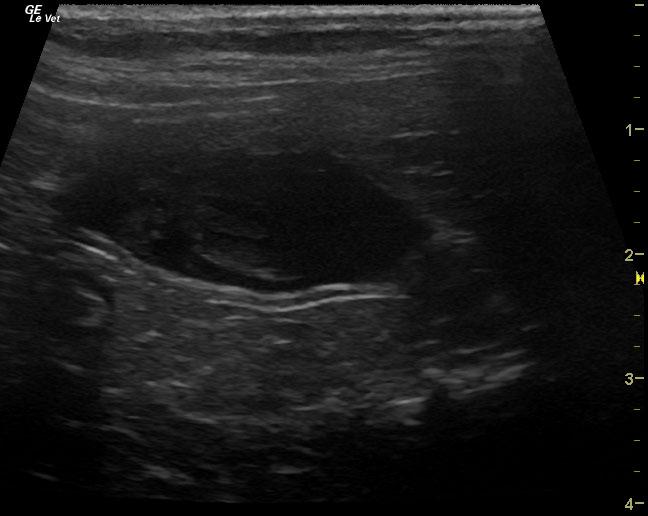

An 18-year-old MN DMH was presented for evaluation of intermittent vomiting and anorexia. A possible abdominal mass was present on abdominal palpation. 1+ calcium oxalate crystals were present on urinalysis. Abnormalities on CBC and serum biochemistry were leukocytosis and hypoproteinemia. T4 was within normal range. Radiographs were within normal limits